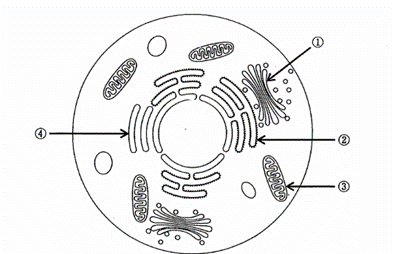

細胞小器官を模式図に示す。ATPを産生するのはどれか。1つ選べ。

a. ①

b. ②

c. ③

d. ④

解答を見る

c